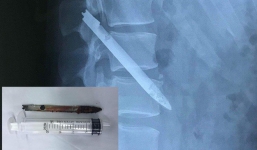

Lưỡi dao bị bỏ quên trong lưng chiến sỹ công an suốt 11 năm